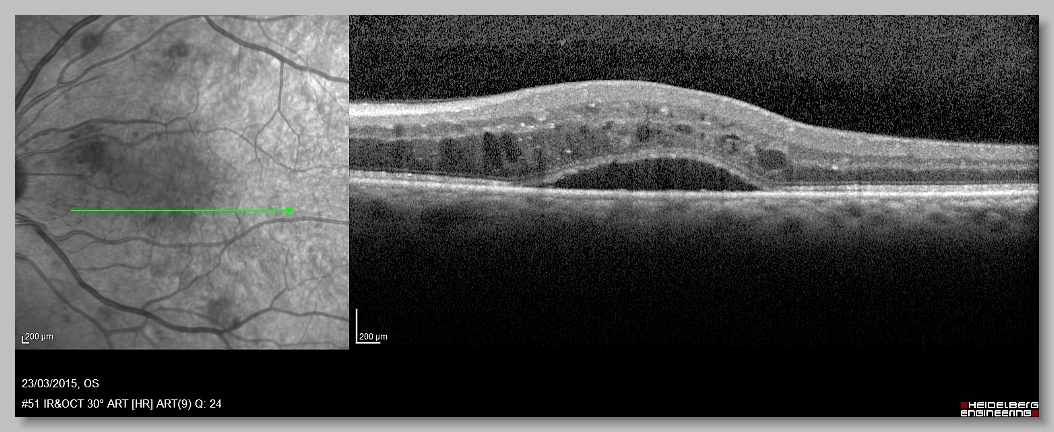

OCT 000 OCT 001 OCT 002 OCT 003

OCT 004 OCT 005 OCT 006 OCT 007

OCT 008 OCT 009 OCT 010 OCT 011